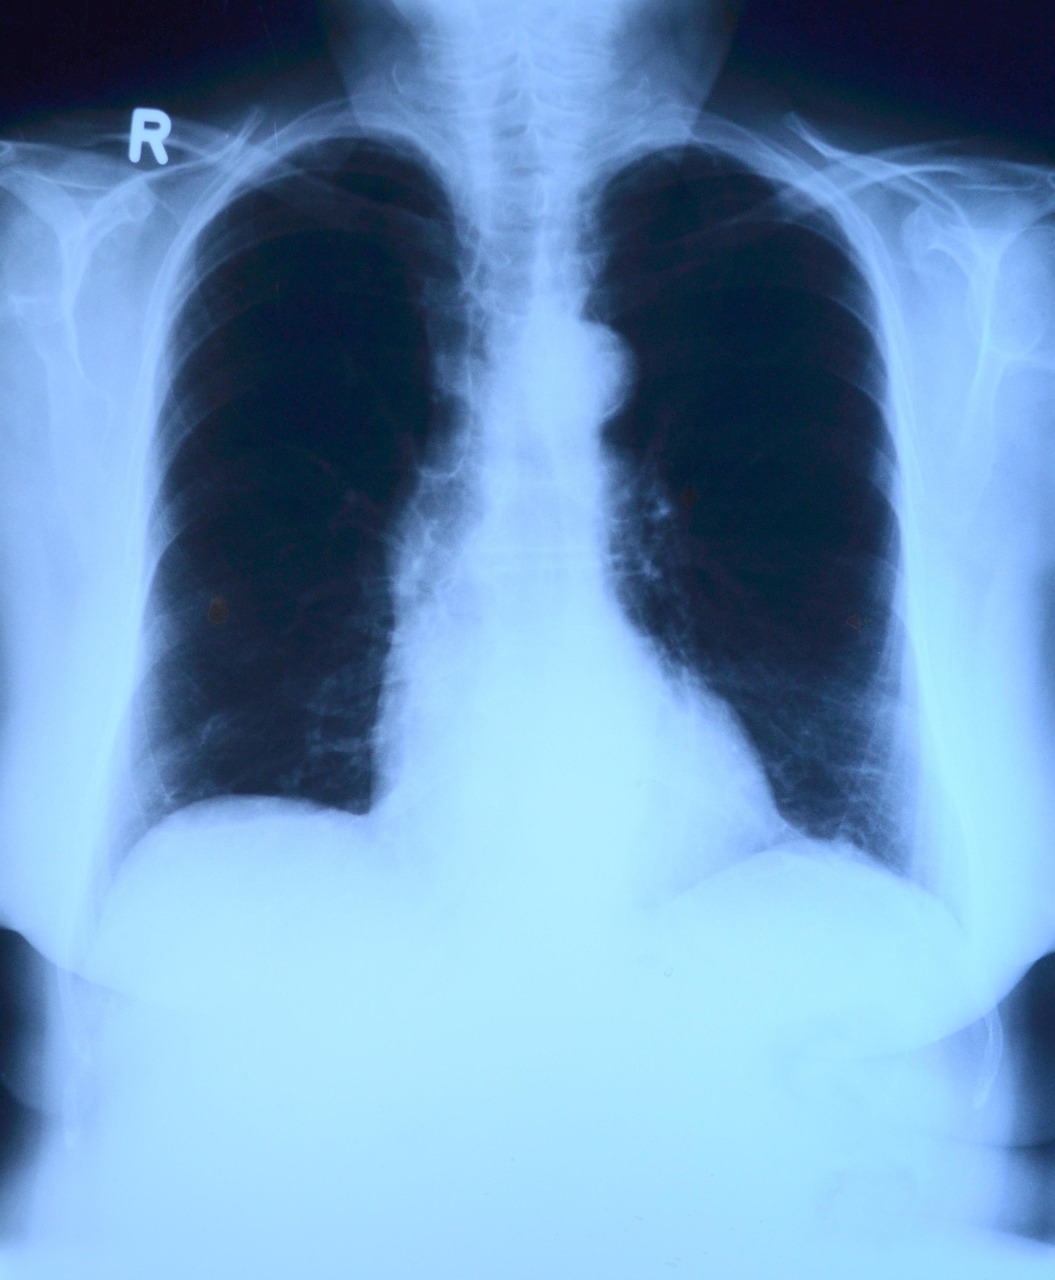

De esta manera, el sistema, denominado Mamba-YOLOvX, se presenta como un aliado rápido y preciso para neumólogos y radiólogos en el diagnóstico de enfermedades pulmonares. En un artículo, publicado en la revista Expert Systems with Applications, los expertos lo presentan y demuestran que la localización de lesiones de diversos tamaños es más rápida y efectiva que con otras herramientas. “En muchas ocasiones, algunas lesiones pulmonares pueden pasar desapercibidas en los exámenes radiológicos, dada la gran dificultad en la interpretación de esta modalidad de imagen médica. Incluso, cuando la enfermedad pasa de un estado inicial a otro de mayor gravedad, la evaluación por parte del experto está sujeta, a menudo, a cierta subjetividad y variabilidad”, indica a la Fundación Descubre el investigador de la Universidad de Cádiz, Daniel Sánchez Morillo, coautor del artículo.

El nuevo modelo combina la información global de la imagen, es decir, el contexto general, como la forma de los pulmones o la posición del corazón, con la información local, los pequeños detalles que pueden indicar lesiones o irregularidades. Esto permite detectar problemas a diferentes escalas.

Además, el sistema incorpora mecanismos de atención espacial y de canal, que funcionan como filtros inteligentes que se concentran sólo en las zonas relevantes de la radiografía y en las características más útiles, ignorando lo que no aporta información. Así, sólo atenderá al pulmón, apartando las costillas o los hombros, y discriminará zonas sanas para centrarse sólo en aquellas que puedan presentar alteraciones.

También incluye bloques de escaneo selectivo, que analizan la imagen en distintas resoluciones y permiten identificar lesiones muy pequeñas, que suelen pasar desapercibidas. Se podría decir que parte de la imagen completa, al mismo tiempo que amplía distintas zonas de la radiografía.